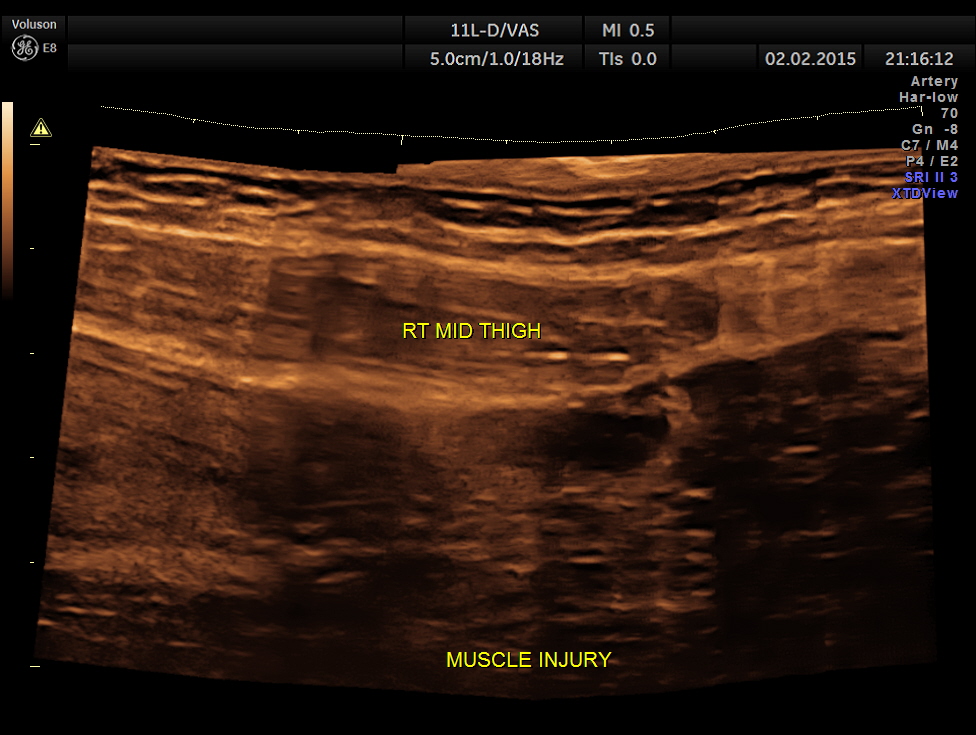

the severely damaged muscles of the thigh